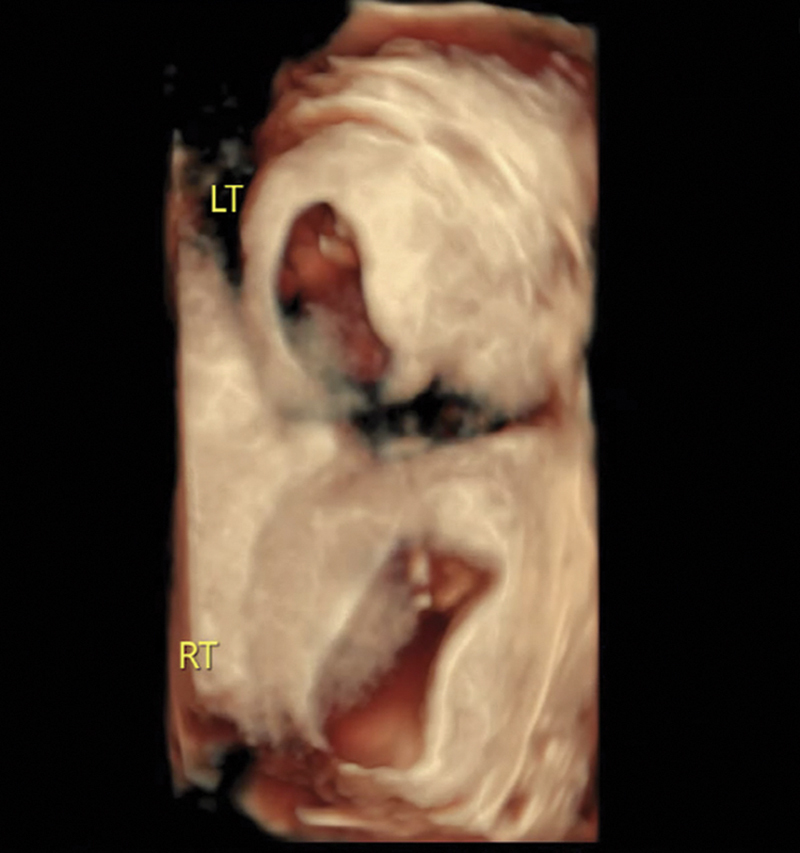

Introduction: A didelphys uterus is a rare Müllerian duct anomaly (MDA) caused by the incomplete fusion of the Müllerian ducts, leading to the formation of two distinct uterine cavities. The occurrence of simultaneous twin pregnancies, with each fetus developing in a separate horn of a didelphys uterus, is estimated at approximately 1 in 1,000,000 cases. This case report describes a rare instance of a spontaneous dichorionic diamniotic twin pregnancy, with one fetus in each horn of a didelphys uterus.

Case description: This is the case of a 35-year-old woman with unilateral renal agenesis who presented with a spontaneous dichorionic diamniotic twin pregnancy, with one fetus in each uterine cavity. This patient's pregnancy complications included intrahepatic cholestasis of pregnancy and rising creatinine levels, leading to a planned cesarean delivery at 36 weeks. The delivery was complicated by intrapartum hemorrhage and the postpartum course was further complicated by sepsis and endometritis.